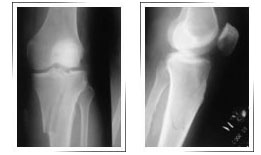

Before Surgery

Before surgery X-ray